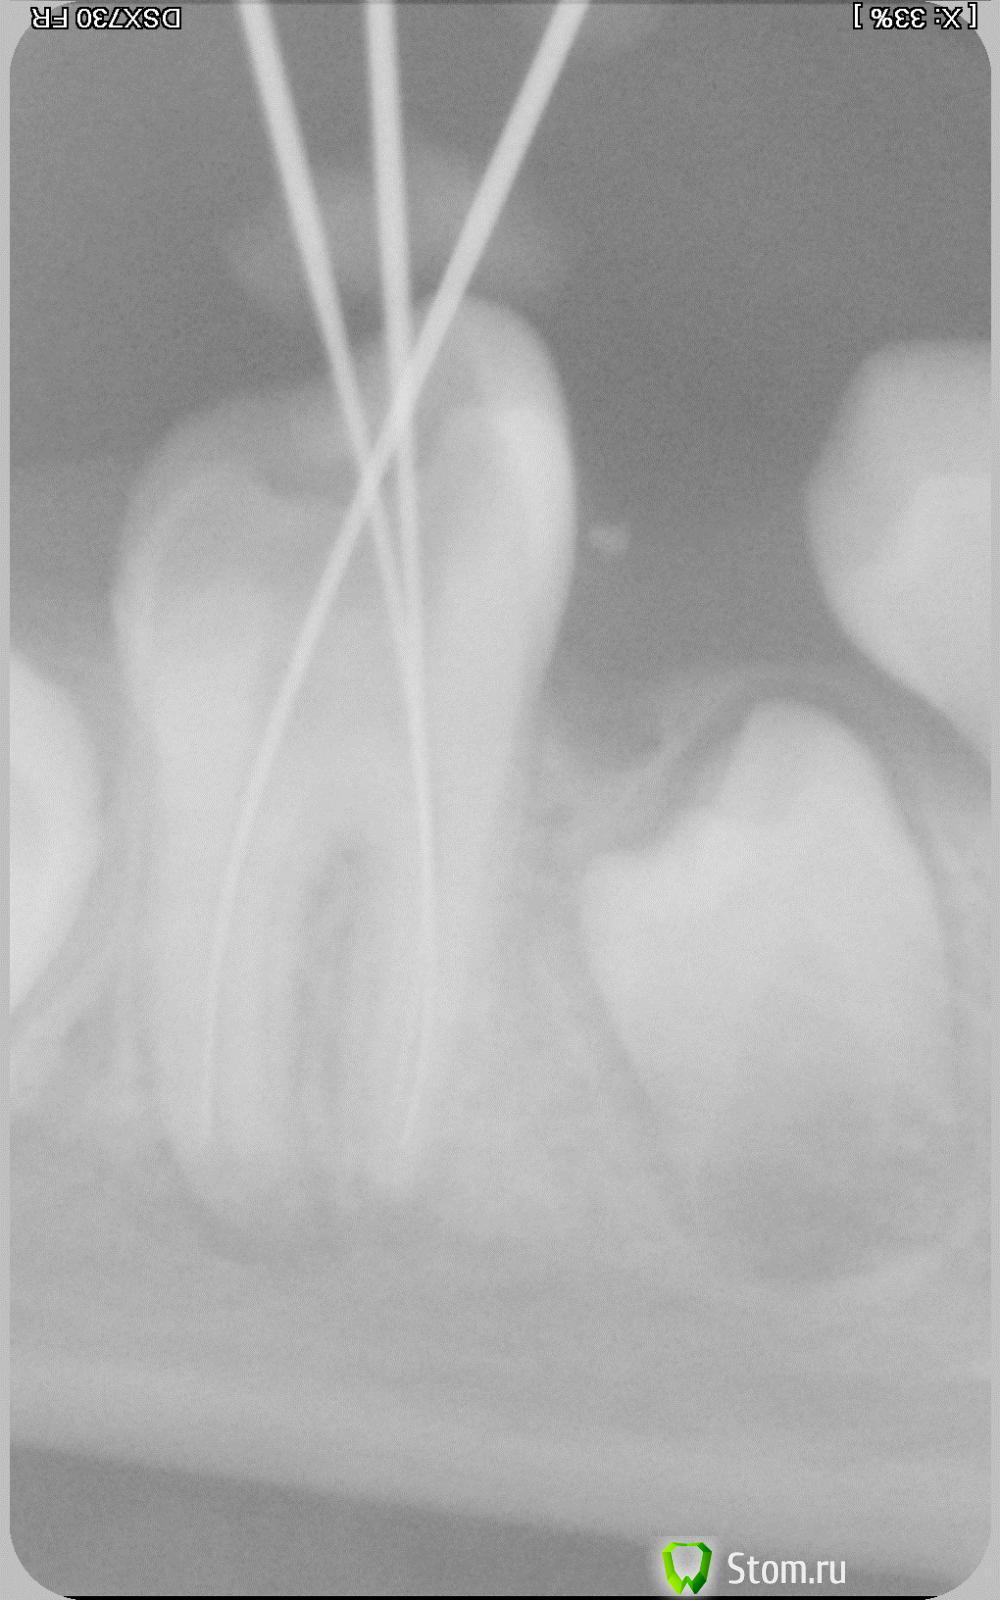

Rat84 Опубликовано 7 апреля, 2012 Поделиться Опубликовано 7 апреля, 2012 Здравствуйте, столкнулся с такой проблемой: пациентка, 9 лет. Месяц назад первый раз пришла на прием с диагнозом острый периодонтит 46. Зуб имел подвижность первой степени, огромную кариозную полость. Сделал снимок, удалил остатки корневой пульпы, расширил каналы и оставил зуб открытым. Удалил оставшийся корень молочного зуба, рядом с причинным. Со слов родителей - боль осталась на прежнем уровне после лечения (хотели ночью поехать и удалить - но не решились). Завтра, на повторном приеме еще раз обработал каналы, провел м/о и оставил ватку с жидкостью эндометазона на устье + временная пломба. Через часов 6 боль прошла, остался лишь дискомфорт при накусывании. Лечение продолжил через пару дней. Еще раз установил файлы, сделал контрольный снимок и запломибровал материалом Calasept. Через 5 дней повторил. Далее - через 7 и 14 дней. В данный момент зуб не беспокоит. При попытке ввести инструмент на всю длину корня (особенно дистального) - резкая боль даже после применения анестетика. В чем проблема, каким постоянным материалом пломбировать и когда, ну или одним вопросом - что делать дальше?Снимки сделаны с периодом в 1 месяц. Ссылка на комментарий

ннэт Опубликовано 9 апреля, 2012 Поделиться Опубликовано 9 апреля, 2012 На мой взгляд очень близко нижнечелюстной канал!!! В каком состоянии была пульпа при первичном обращении? Снимки тоже качественно не просматриваются. но корни сформированы. Причина болевой чувствительности может быть либо в том что выходите за широкий апекс прямо в н/ч канал, или в том что не доубрали гангренозную пульпу. Используйте доп методы анестезии + показания аплока Ссылка на комментарий

Джима Опубликовано 15 апреля, 2012 Поделиться Опубликовано 15 апреля, 2012 наконец-то с компа захожу и вижу снимки. +1 к нижнечелюстному каналу и плохому качеству снимков. но мне кажется, верхушки всё же не закрыты, дистальный так точно. Ссылка на комментарий

Паращук Роман Опубликовано 22 апреля, 2012 Поделиться Опубликовано 22 апреля, 2012 Рентгенограммы не удов. Рен-мма-это срез в одной плоскости. Думаю до канала н\ч как до Китая. Имеется остаточный пульпит и неадекватное обезболивание. По тому что видел,работайте с зубом как после зав-нной апексофикации. Если не удастся сделать апикальный упор на уровне макс 40-го разм. ,мта в апикальную часть+ ваш метод обтурации к\к. Ссылка на комментарий